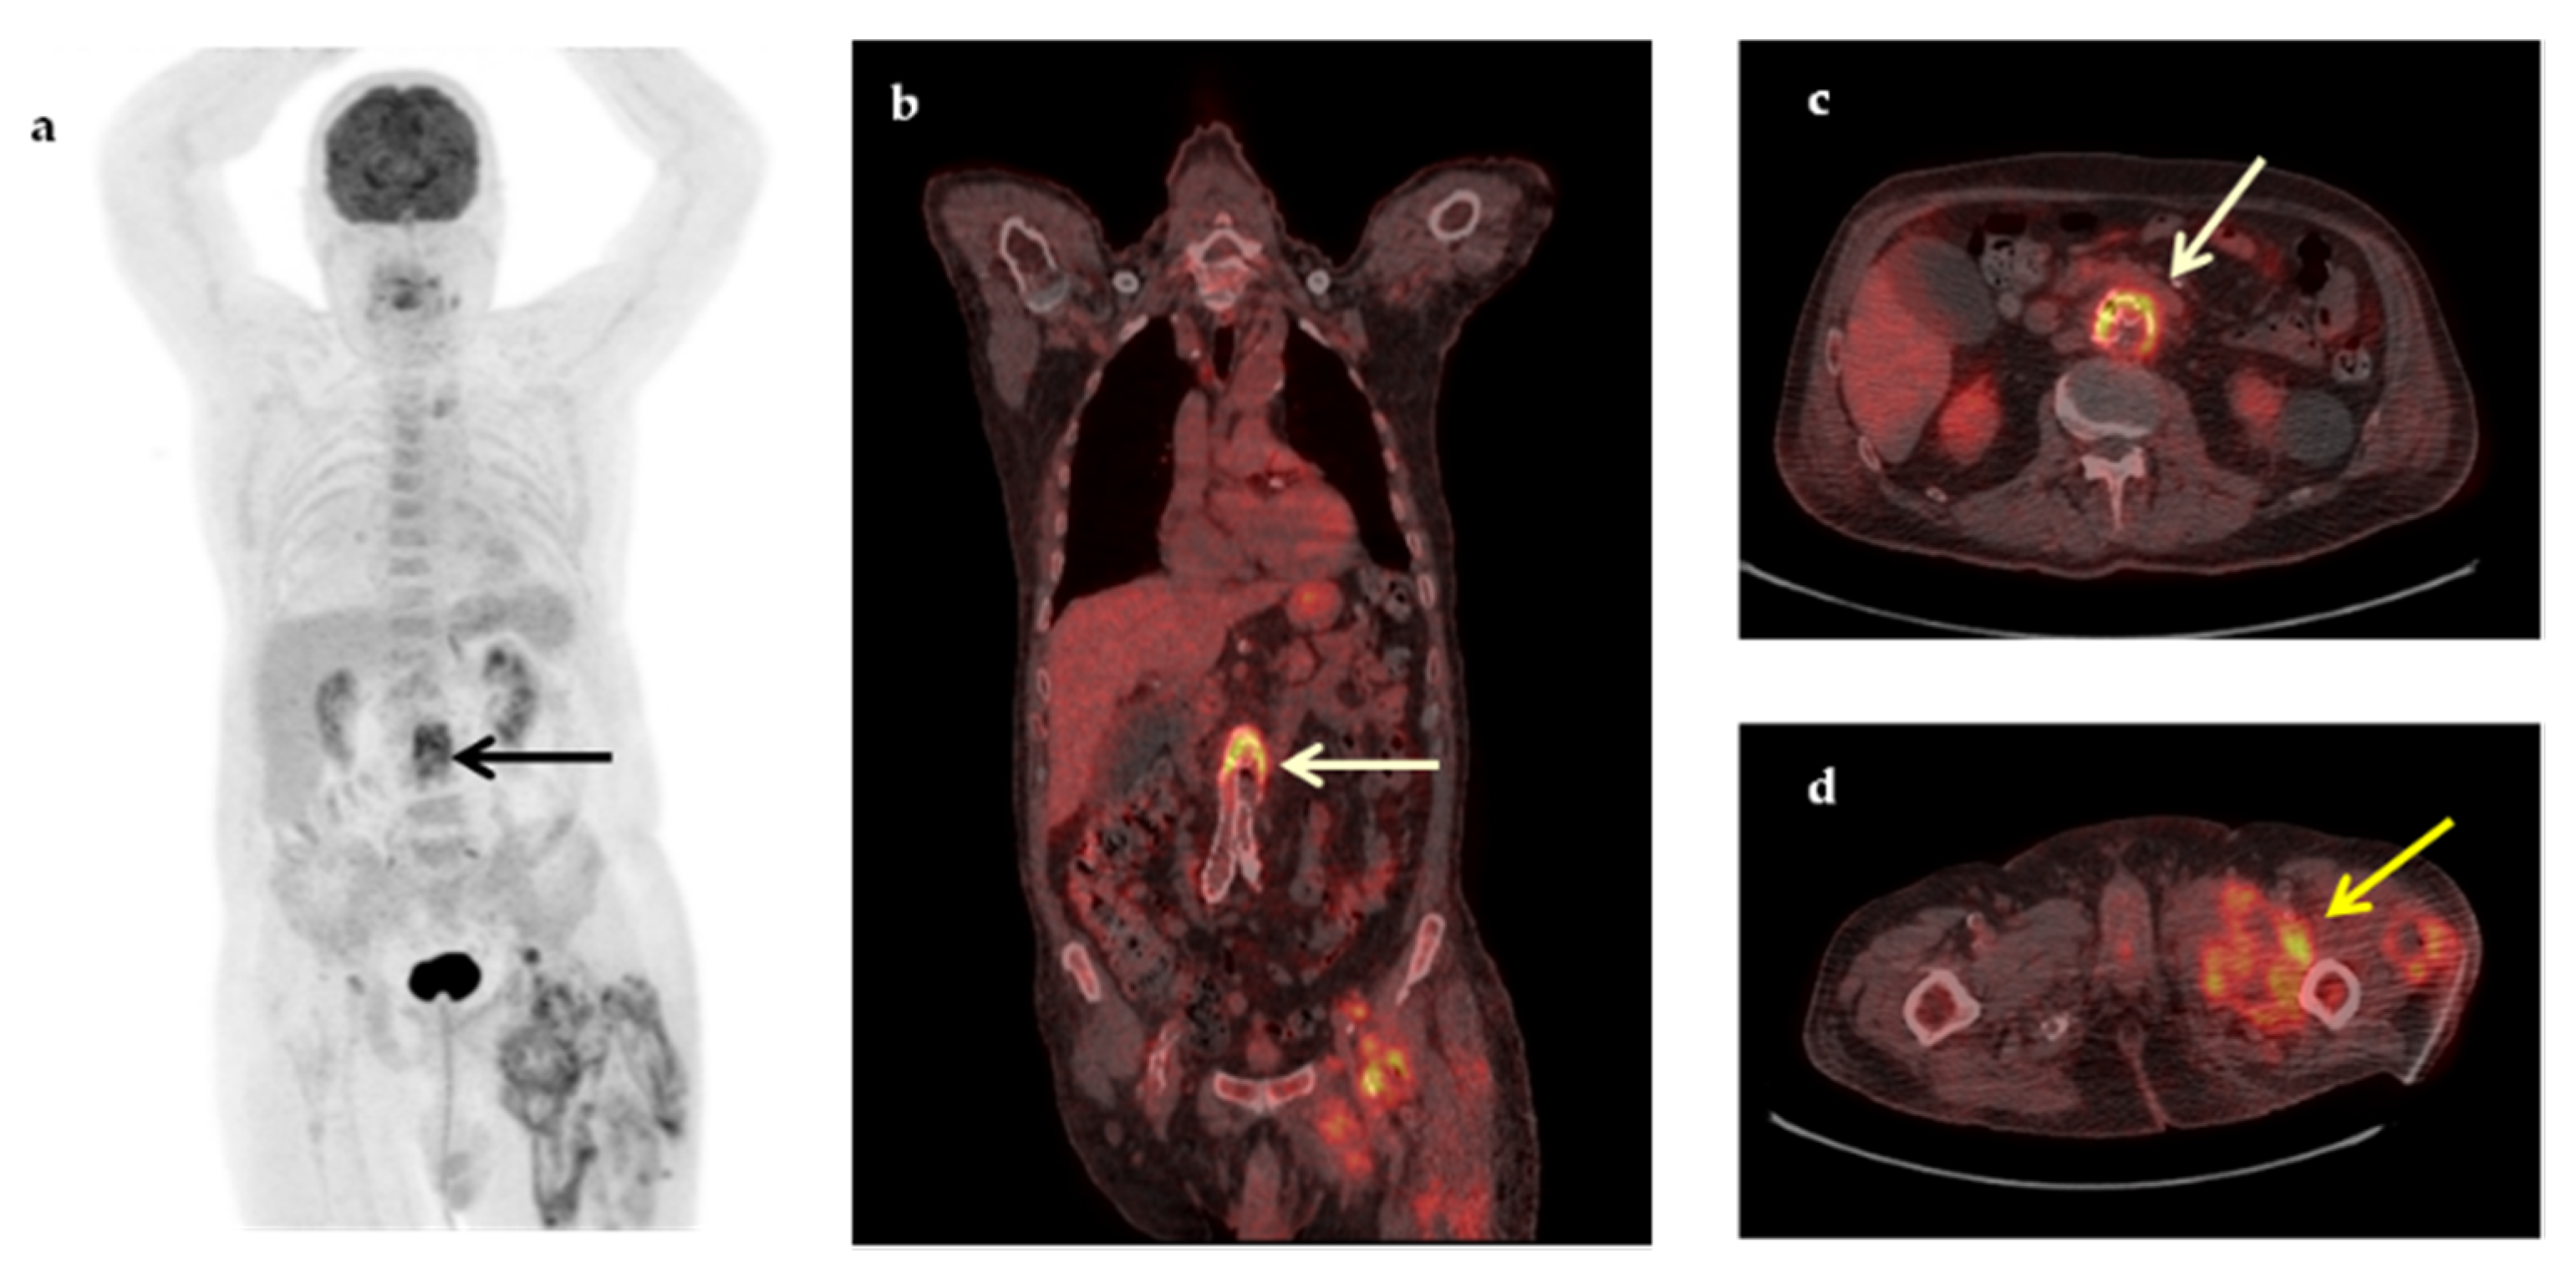

| Abdominal abscesses | 4 |

| Infectious cyst in polycystic renal disease | 3 |

| Pneumonia/inflammation of bronchiectasis cysts | 3 |

| Vascular graft infection | 3 |